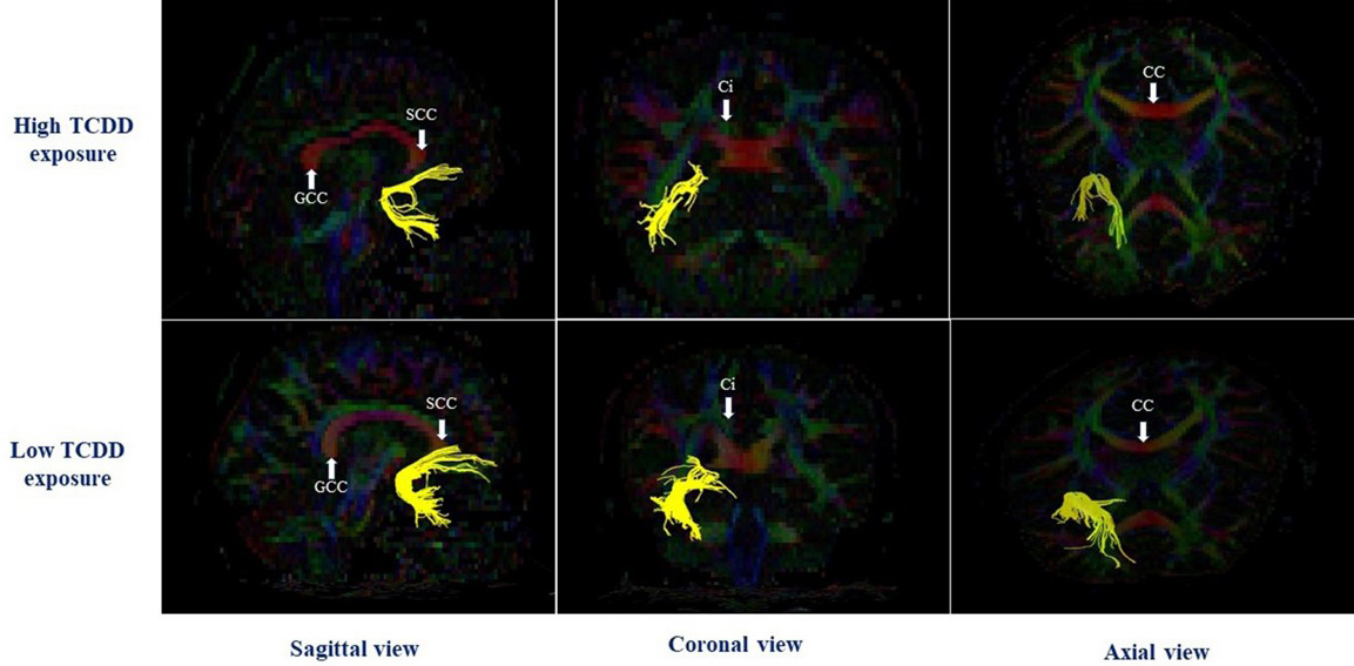

DTI(diffusion tensor image)

脳の神経繊維の配向や経路を画像化し評価する技術です。神経科学、臨床研究、発達研究などで用いられています。​

脳内の水分子が神経線維に沿ってどのように拡散するかを拡散強調画像で測定し、その方向性を三次元的にモデル化し脳内の神経線維の配向や構造を推定します。​

VBMと同様に、fMRIやPETなどと合わせて脳機能と脳構造の関係を理解するために用いられることもあります。

ダイオキシン曝露レベルと左側の海馬領域における神経繊維(黄色)について評価しています。

上:ダイオキシン類の1つであるTCDDの血中濃度が高いグループの評価

下:ダイオキシン類の1つであるTCDDの血中濃度が低いグループの評価​

Impacts of dioxin exposure on brain connectivity estimated by DTI analysis of MRI images ​in men residing in contaminated areas of Vietnam より引用